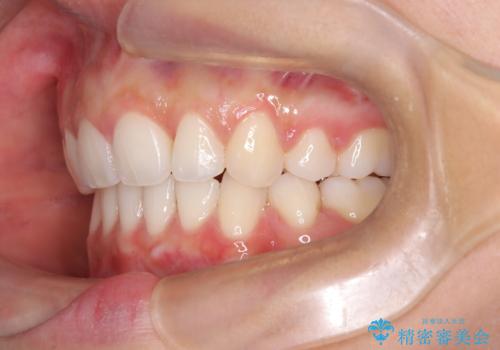

2. 【審美ワイヤー】口元を下げたいの治療中